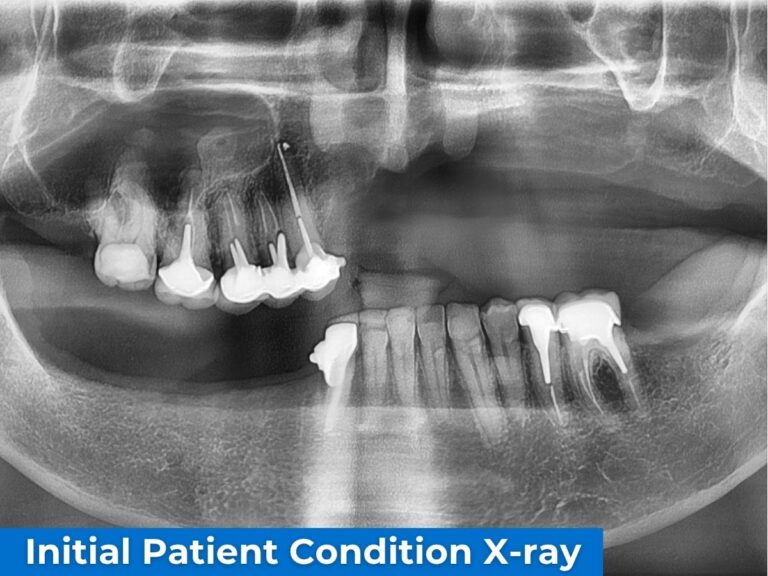

Dr Russo - Initial Patient Condition X-ray

Clinical photographs illustrating severe aesthetic and functional impairment, and a panoramic radiograph demonstrating advanced bone deficiency.

Three-dimensional radiographic analysis revealed a particularly critical anatomical situation.

In the left maxillary sector (sector 2), residual bone was virtually absent in the posterior regions. The alveolar ridge appeared extremely thin, with insufficient height and width to support conventional implant stabilization.

In contrast, the right maxillary sector (sector 1) exhibited a distinct configuration, resulting in marked asymmetry between the maxillary halves. This asymmetry was not only volumetric but also involved the position of the sinus cavities.

The prior trauma had significantly altered the osseous architecture, leading to asymmetric sinus pneumatization with sinus floors at different levels on each side.

Residual bone density was low, and the maxillary ridge was severely resorbed. Under these conditions, not only were conventional implants contraindicated, but extensive bone grafting strategies were also considered unrealistic, given both the anatomical alterations and the limited structural capacity of the recipient site.